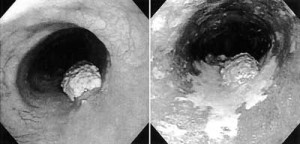

図3 食道造影検査バリウムをのんで撮影した食道の写真。ポリープようの病変が食道がん 図4 内視鏡検査内視鏡でみた食道。左の白いポリープが食道がん |

内視鏡検査は発見に一番有力な検査です。図4は内視鏡写真です。

左側は通常の観察で発見された白色のポリープようの食道がんです。右側はルゴールという色素を散布した写真で、白色域が広がっているのがわかります。この白色域全部が食道がんです。

このように、内視鏡検査では、正常な食道粘膜はルゴールに反応して黒く染まるという特徴がある一方で、食道がんになっているところはルゴールに染まらず、白い粘膜としてはっきりと観察できるのです。

最終診断は、そのルゴールに染まっていない細胞組織を少し採って調べ、顕微鏡を使ってがん細胞を証明するのです。